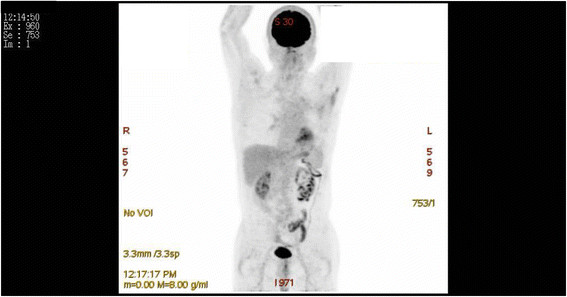

The patient refused postoperative adjuvant chemotherapy and radiation therapy, although this was recommended. The patient has resumed his daily routine and has been followed-up for 64 months. The most recent positron emission tomography scan revealed no postsurgical recurrence at any site for >5 years (Figure 3).

Figure 3.

A positron emission tomography scan shows that the patient remains recurrence free 5 years after extrapleural pneumonectomy.